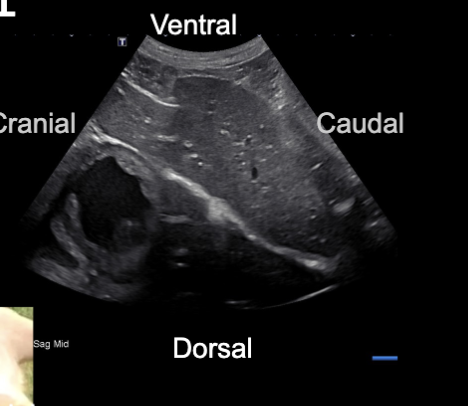

Sagittal image

Cranial to the left

Caudal to the right

Ventral at the top of image

Dorsal at bottom of image

Sagittal